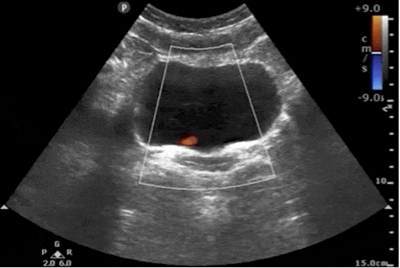

Lung PoCUS and LV Function

In addition to the cardiac windows, lung ultrasound (LUS) can also provide valuable indirect information about LV performance. LUS is highly sensitive to detect early or subtle increases in left ventricular end diastolic filling pressures (LVEDP) [24].

In the setting of LV systolic dysfunction or congestive heart failure, elevated LVEDP leads to pulmonary congestion, which manifests on LUS as the progressive appearance of B-lines. B-lines occur as the edema or excess extravascular lung water interact with air-filled alveoli to create a reverberation artifact. The distribution and severity of B-lines correlate with the degree of pulmonary interstitial edema or fluid overload and, by extension, can reflect deterioration in LVfx.

Integrating LUS findings with cardiac PoCUS can provide a more comprehensive assessment of LVfx.

For details on performing and interpreting LUS in the context of heart failure and pulmonary congestion, please refer to the dedicated KidSONO Interstitial Disease module